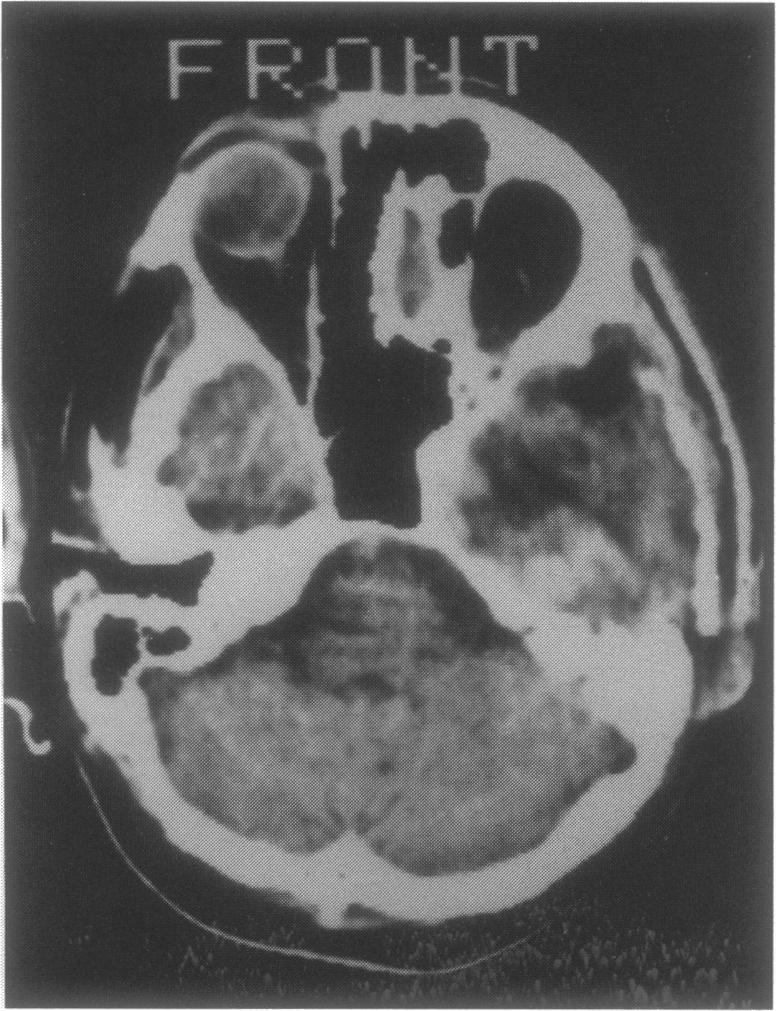

A case of a basal middle fossa giant cell tumor occurring in a 46-year-old man is described. The lesion appeared at the computed tomography (CT) scan examination as an hypodense mass with a peripheral "ring-like" enhancement, and no evident erosion of the skull base. The tumor, which infiltrated the basal temporal parenchyma, was removed via a temporal transzygomatic craniotomy, and extensive drilling of the petrous bone. Despite the occurrence, of significant postoperative complications, the patient ultimately showed a good clinical outcome, with no signs of recurrence at the 1-year follow-up CT scanning. The clinical and diageostic aspects and the management policy, of this rare lesion are discussed.

本文描述了一例发生在一名46岁男性的颅中窝底巨细胞瘤。在计算机断层扫描(CT)检查中,该病变表现为低密度肿块,周边有“环状”强化,且颅底无明显骨质侵蚀。肿瘤侵犯颞叶底部实质,通过颞部经颧弓开颅术及广泛磨除岩骨将其切除。尽管术后出现了严重并发症,但患者最终临床效果良好,术后1年的CT扫描未见复发迹象。本文还讨论了这种罕见病变的临床和诊断方面以及治疗策略。